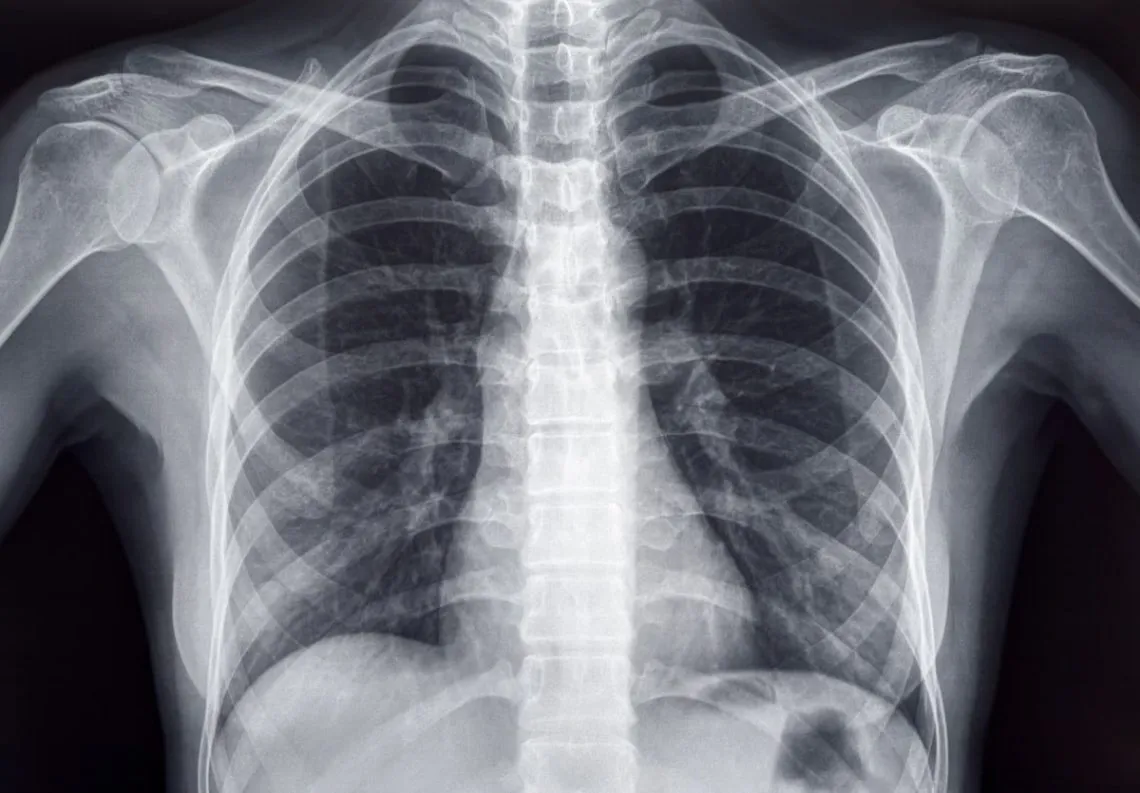

RTG klatki piersiowej: Czy zawsze jest zlecane i co może wykazać?

Rentgen klatki piersiowej (RTG) to jedno z podstawowych badań obrazowych w pulmonologii. Nie zawsze jest zlecane od razu, ale często stanowi pierwszy krok w diagnostyce, gdy podejrzewam zmiany w płucach. Jest to szybkie i łatwo dostępne badanie, które pozwala mi ocenić ogólną strukturę płuc, serca i śródpiersia. Na zdjęciu rentgenowskim mogę dostrzec m.in. zmiany zapalne (jak w zapaleniu płuc), obecność płynu w opłucnej, powiększenie węzłów chłonnych czy nawet wstępne zmiany nowotworowe. Choć ma swoje ograniczenia, jest niezwykle cenne jako badanie przesiewowe.